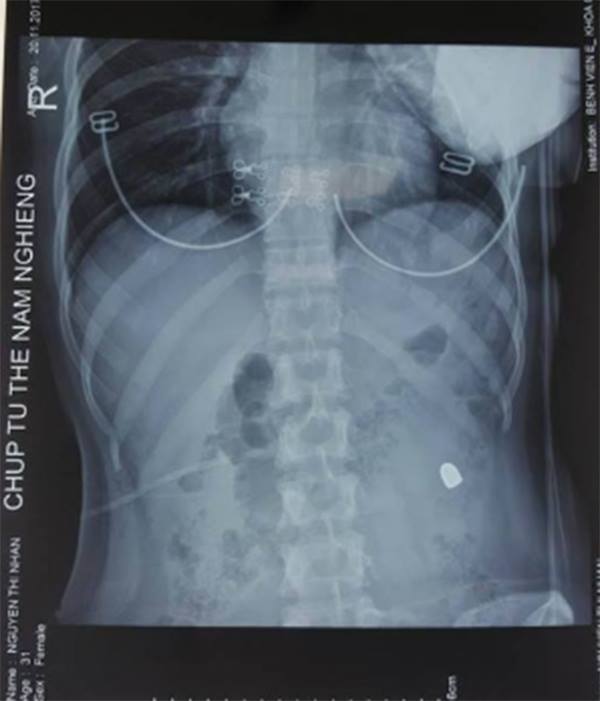

Phim chụp X-quang.

Các bác sĩ lập tức cho bệnh nhân đi siêu âm, chụp X-quang. Kết quả cho thấy, siêu âm có nhiều dịch trong ổ bụng. X-quang thấy một đầu đạn nằm mạn sườn trái. Các bác sĩ chẩn đoán vết thương thấu bụng nghi ngờ thủng tạng rỗng. ThS.BS Trần Thượng Việt - Khoa Phẫu thuật thận tiết niệu và nam học (Bệnh viện E) là người trực tiếp tiến hành ca mổ cho biết, tổn thương ổ bụng mà bệnh nhân này gặp phải là thủng đại tràng ngang 4 lỗ.